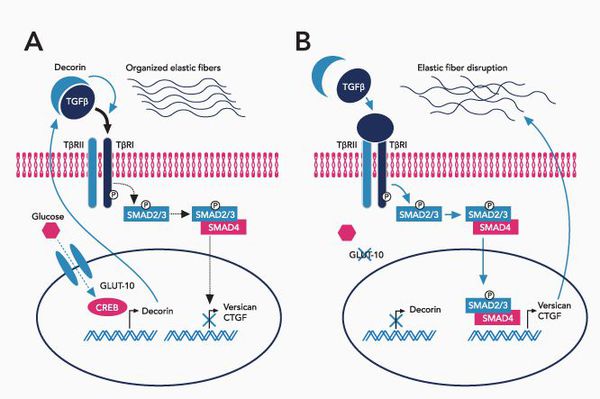

Sindrom marfana tema nauchnoj stati po klinicheskoj medicine chitajte besplatno tekst nauchno issledovatelskoj raboty v elektronnoj biblioteke kiberleninka (Тип файлу jpg)

Sindrom Marfana Tema Nauchnoj Stati Po Klinicheskoj Medicine Chitajte Besplatno Tekst Nauchno Issledovatelskoj Raboty V Elektronnoj Biblioteke Kiberleninka